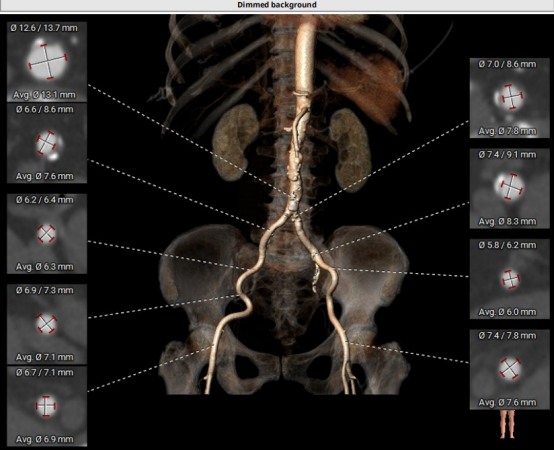

CT結(jié)構(gòu)評估

患者為功能性二葉瓣,瓣葉增厚,輕度鈣化,鈣化主要集中在左竇瓣葉上,左冠脈高度較低,結(jié)合瓣葉長度,竇部結(jié)構(gòu)綜合評估左冠風(fēng)險較低,但左冠瓣葉瓣尖處有鈣化團塊,在球擴以及瓣膜釋放時仍需注意左冠灌注情況,由于鈣化團塊位置特殊,建議做冠脈保護處理,右側(cè)股動脈作為主入路,穿刺點位于股骨頭中段即可。

采取局麻+鎮(zhèn)靜麻醉方式,避免氣管插管對循環(huán)打擊;預(yù)裝VenusA L26瓣膜,患者心功能較差不進行球囊預(yù)擴張,直接放瓣膜;升主動脈稍寬,注意器械通過,必要時snare輔助;建議行左冠保護;右股動脈作為主入路。